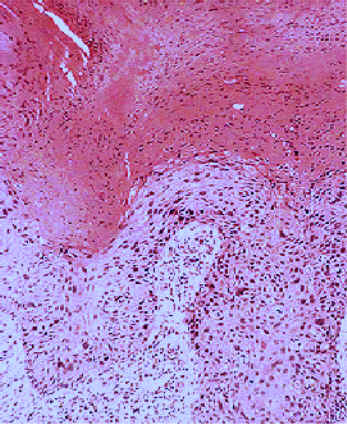

Acantosis: Aumento del grosor de la epidermis. también se observa hiperqueratosis, aumento del grosor de la capa córnea.

| Hiperqueratosis (aumento del grosor

de la capa córnea), Paraqueratosis (persitencia de los núcleos

de los queratinocitos en la capa córnea) y Acantosis (aumento

del grosor de la capa espinosa).